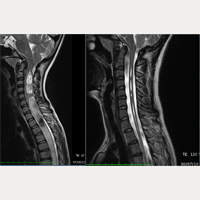

原发性脊柱侧弯

自1993年10月到今天,研究所已经有超过2000位脊髓空洞症、小脑扁桃体下疝畸形、脊柱侧弯患者接受了终丝系统®医疗法(FILUM-SYSTEM®)的手术。